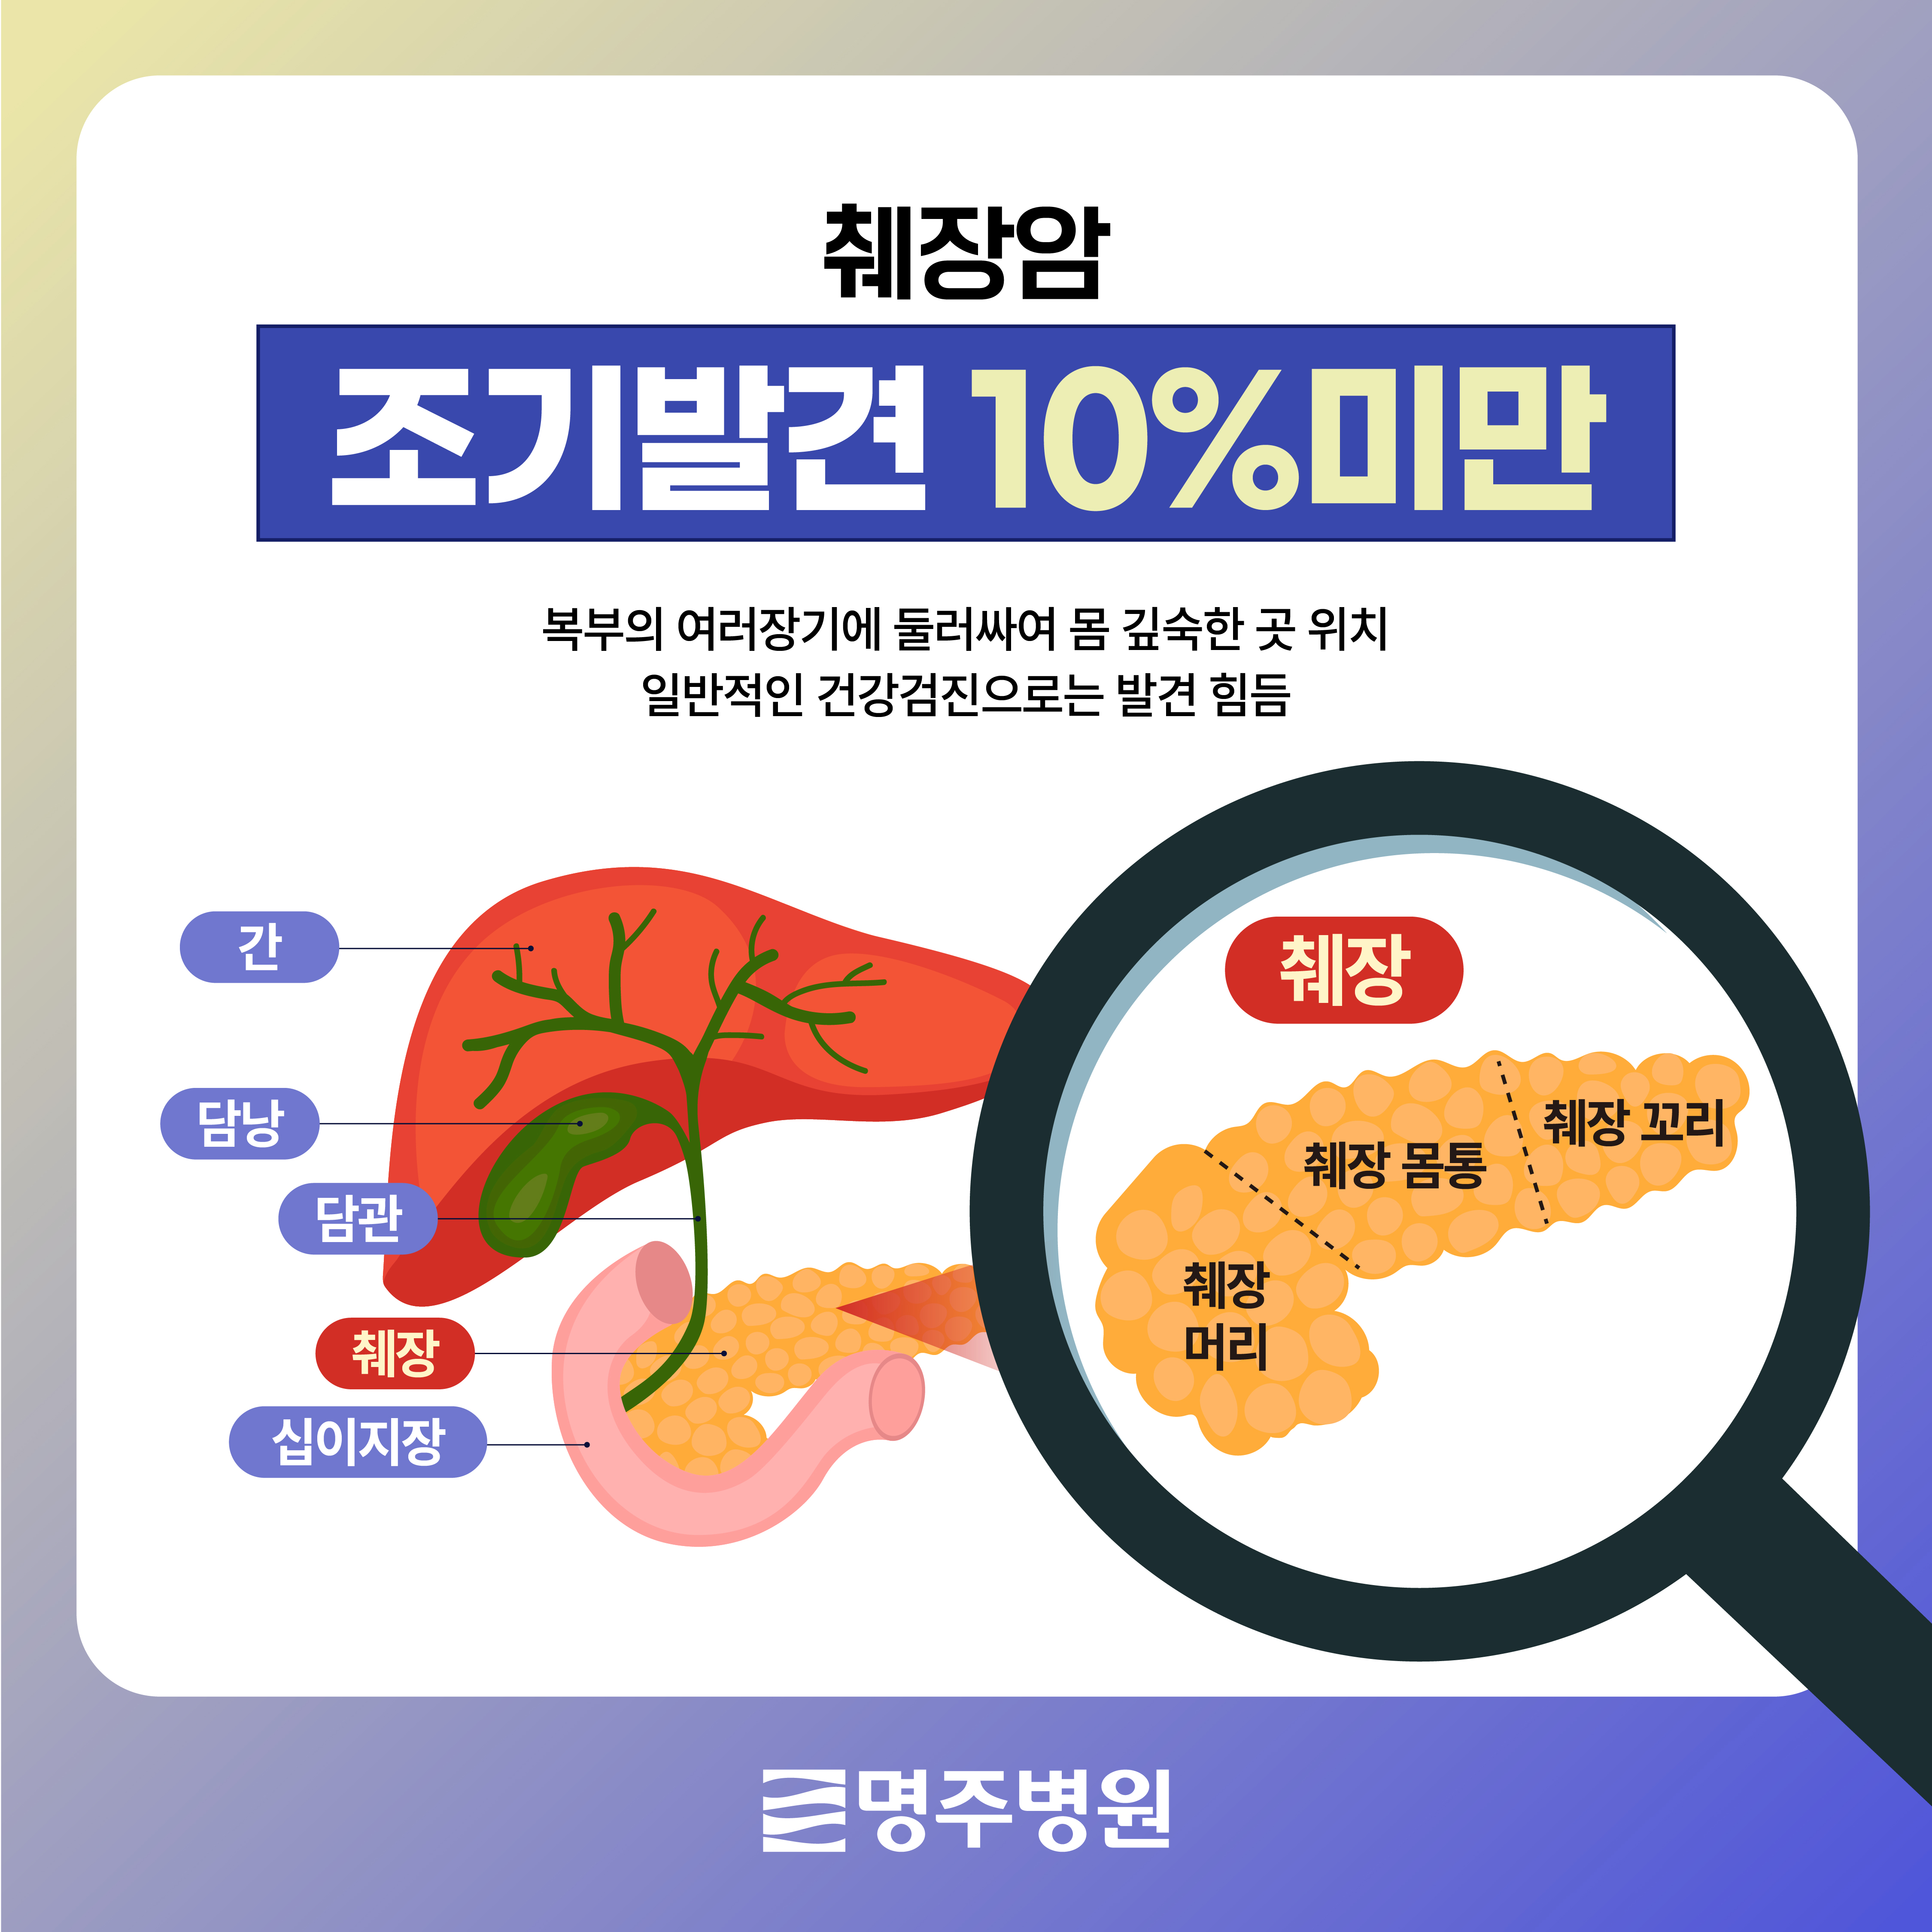

췌장은 머리, 몸통, 꼬리의 세 부분으로 나누어지며, 췌장암은 췌장에 생긴 종양을 뜻하고, 췌장의 머리에서 가장 빈번하게 발생하며, 특히 췌관세포에서 발생하는 췌관선암종이 가장 흔하게 발견됩니다.

많은 장기에 발생하는 암이 그러하듯이 암이 발생되는 초기, 환자분께서 자각할 만한 특별한 증상이 나타나지가 않으며, 특히 췌장이 복부 가장 깊숙하게 위치해 있으므로, 특징적인 증상을 느끼기가 어려울 수가 있습니다.